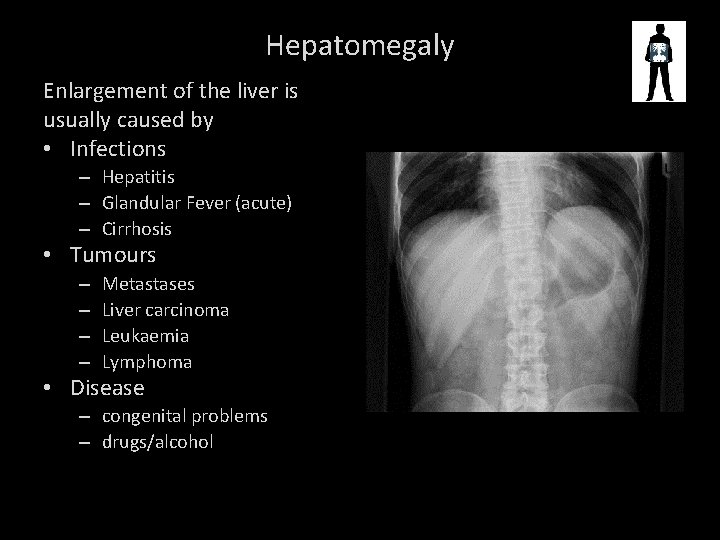

Hepatomegaly Enlargement of the liver is usually caused by • Infections – Hepatitis – Glandular Fever (acute) – Cirrhosis • Tumours – – Metastases Liver carcinoma Leukaemia Lymphoma • Disease – congenital problems – drugs/alcohol